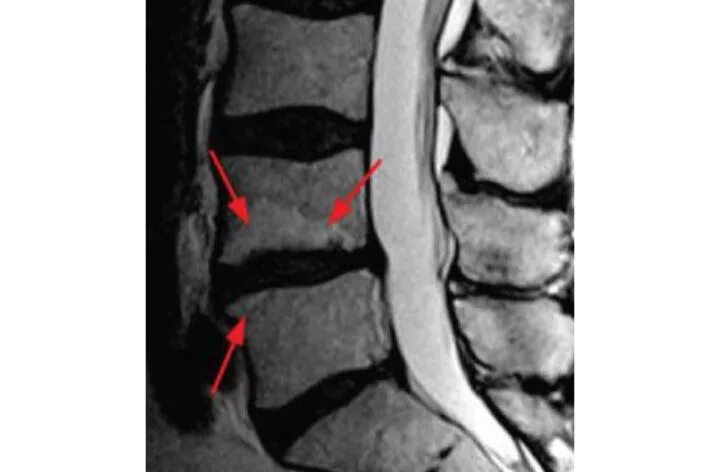

Мрт крестово поясничного отдела